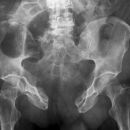

Coxarthrose